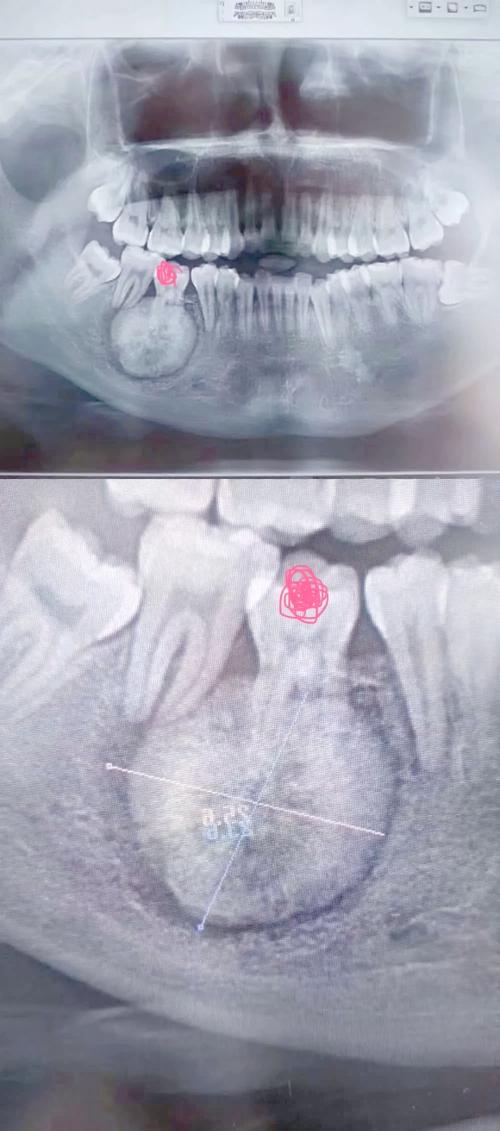

全景片还能识别潜在风险,如邻牙牙根吸收、囊肿、埋伏牙与重要解剖结构(如下颌神经管)的位置关系,避免拔牙时损伤神经或引发并发症,尽管全景片为二维影像,对牙根腭侧/颊侧倾斜、骨皮质厚度等细节显示不如CBCT,但其辐射剂量低、拍摄便捷、费用较低,仍是正畸减数前不可或缺的“第一道检查关卡”,可以说,全景片如同正畸减数治疗的“导航地图”,通过清晰呈现口腔解剖结构,帮助医生精准规划拔牙方案,确保治疗安全与效果,是每一位需要减数的正畸患者必做的关键检查。